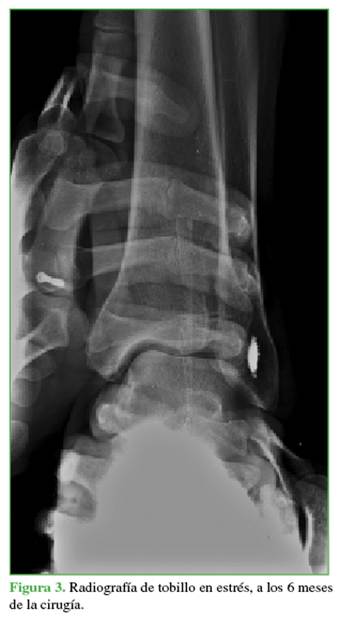

Los pacientes con traumatismos de tobillo fueron evaluados con radiografías convencionales y, una vez descartadas las fracturas, se procedió al examen clínico de la inestabilidad lateral mediante varo de la articulación tibio-astragalina. Cuando este generaba una sospecha clínica, se confirmaba el diagnóstico con las radiografías en estrés, tomadas con el paciente en relajación máxima y una dorsiflexión de no más de 10° para relajar el ligamento calcáneo-peroneo. Se ejerció varo del retropié manteniendo firme la región distal de la pierna y se hizo en forma comparativa con el tobillo sano (Figura 1).

Para evaluar la reparación del complejo ligamentario lateral, a los 6 meses de la cirugía, se solicitó una radiografía en estrés (Figura 3). En la evaluación clínico-funcional, se utilizaron la escala de la AOFAS (American Orthopaedic Foot and Ankle Society) y la escala analógica visual.